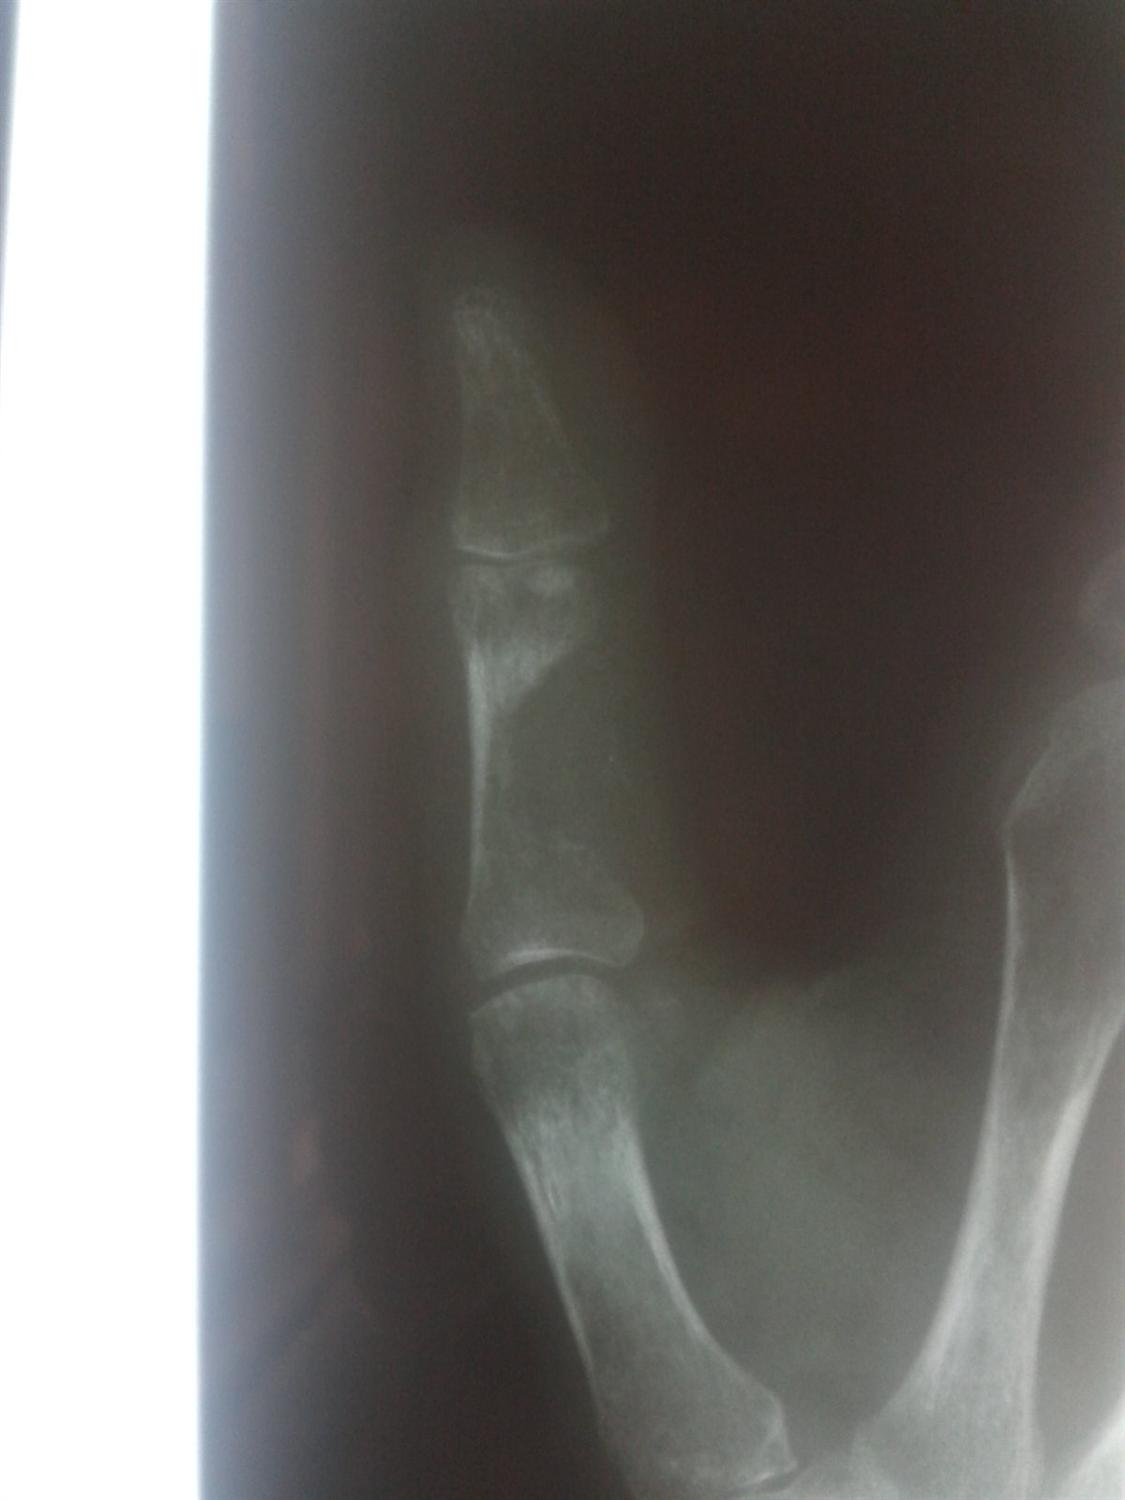

THA Periprosthetic Fracture Recon Orthobullets

Crush Fracture Orthobullets Web these fractures are commonly caused by trauma or crush injuries. Web phalanx fractures are common hand injuries that involve the proximal, middle or distal phalanx. Crush/ hyperflexion injury distal phalanx with associated nailbed injury (often seemingly mild), and injury to growth. The middle finger is most often affected, followed by the. Diagnosis can be confirmed with orthogonal. Web osteoporotic vertebral compression fractures are very common fragility fractures of the spine that affect up to 50% of people over 80 years. 14, 15 mri or computed. Metatarsal fractures are among the most common injuries of the foot that may occur due to trauma or. Web these fractures are commonly caused by trauma or crush injuries. Web crush injuries of the hand involve damage to multiple structures within the hand, loss of tissue, devascularisation and. Web fractures of the metacarpal heads are relatively uncommon and usually result from a direct blow, crush injury, or projectile. Web magnetic resonance imaging (mri) can help distinguish benign from malignant fractures and determine the timing of the fracture, because recent fractures display edema.